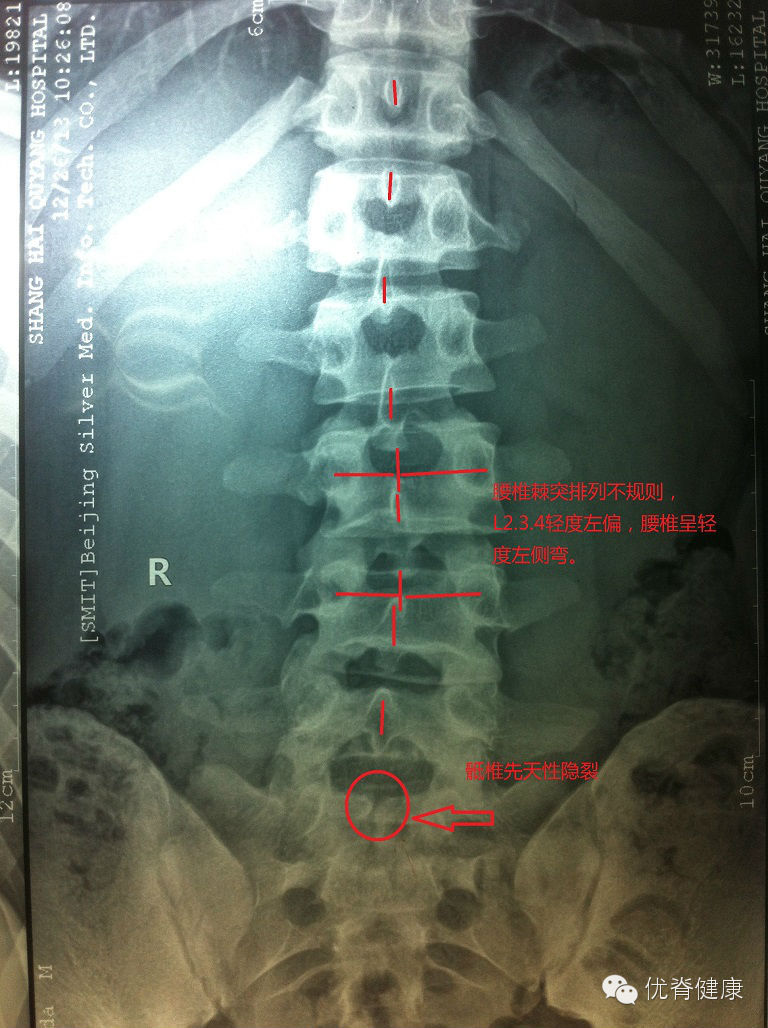

环枢关节错位,颈椎生理曲度反弓,轻度右侧弯,部分骨质增生;腰椎轻度左侧弯,伴骶椎S1隐裂;颈腰部肌群不同程度劳损,以上颈部及下腰部肌群劳损较为明显。

评估分析:颈椎软组织劳损,伴环枢关节错位,颈椎生理曲度反弓,伴轻度右侧弯。腰椎轻度左侧弯,腰肌劳损。